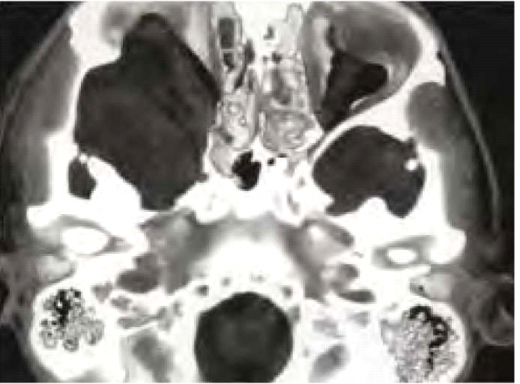

גליומות של המערכת האופטית מתפתחות בכ-15% מחולי נוירופיברומטוזיס מסוג 1 ועשויות לערב כל חלק של הנתיב האופטי, לרבות עצבי הראייה, כיאזמה (Chiasm), מסילות הראייה (Optic tracts) ומסלולי הראייה בתוך המוח. גידולים אלה מאובחנים לרוב בשנים הראשונות של החיים (בממוצע בגיל 4) ומתבטאים קלינית בירידה בחדות הראייה, פגיעה בשדות הראייה ולעתים בבלט עין (Proptosis) ובהתפתחות מינית מוקדמת במקרים של מעורבות תת-רמה (Hypothalamus). כיוון שילדים קטנים בדרך כלל אינם מתלוננים על ירידה בראייה, בדיקת עיניים תקופתית היא חובה בקרב הילדים החולים או חשודים כחולים בנוירופיברומטוזיס מסוג 1. במקרה של סימנים אובייקטיביים (Objective) של פגיעה במערכת הראייה [ירידה בחדות הראייה, סימנים של ניוון (Atrophy) של עצבי הראייה, פגיעה בשדה הראייה] יש צורך בבדיקת הדמיה בתהודה מגנטית של המוח וארובות העיניים (תמונה 5). אין כל הצדקה לשלוח ילדים לבדיקת טומוגרפיה ממוחשבת (CT, Computed Tomography) של הראש. מבחינה היסטולוגית, גליומות של המערכת האופטית הינן אסטרוציטומות פילוציטיות (Pilocytic astrocytoma), בעלות דרגת ממאירות נמוכה (1 WHO). ברוב המכריע של המקרים אין צורך בביופסיה והאבחנה נעשית על סמך המידע הקליני וההדמיתי. בדרך כלל, לגליומות של המערכת האופטית מהלך קליני שפיר. הן יכולות לגרום לפגיעה משמעותית בתפקוד הראייה בעיקר בעשור הראשון של החיים. בהמשך, גדילתן לרוב נעצרת ותפקוד הראייה נשאר יציב. במיעוט המקרים הגידולים גדלים בקצב גבוה ועלולים לפגוע בצורה קשה בראייה, עד כדי התפתחות של עיוורון מוחלט. הטיפול באותם מקרים כולל שימוש בתרופות כימיות (לרוב Vincristine ו-Carboplatin) עם נטייה להימנע משימוש בקרינה. התערבות ניתוחית נעשית במקרים של בלט עין קשה או לחץ תוך גולגולתי מוגבר בלתי נשלט.

- נגעים גרמיים אופייניים כגון דיספלזיה של עצמות היתד בגולגולת או אי חיבור של עצם השוקה